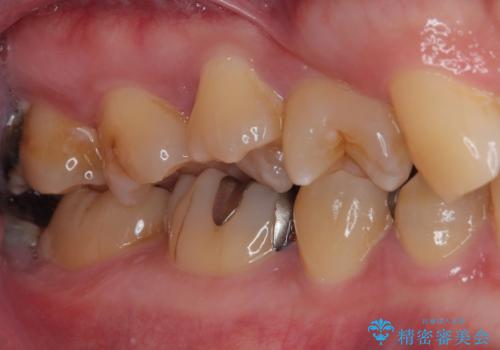

- 金属の詰め物が外れたので、虫歯の治療がしたいとのことで来院された患者様です。ほかの部位の治療などもあったため、コンポジットレジンによる応急処置を初診時に行いました。

ほかの部位の治療が一段落ついたのでセラミックインレー修復による虫歯治療を行っていくことにしました。

歯と歯の間の虫歯をコンポジットレジンや保険のメタルインレーで治すと段差ができたりして清掃性が悪くなるので、セラミックインレー修復やゴールドインレー修復などの適合の良い詰め物で治療することをオススメします。